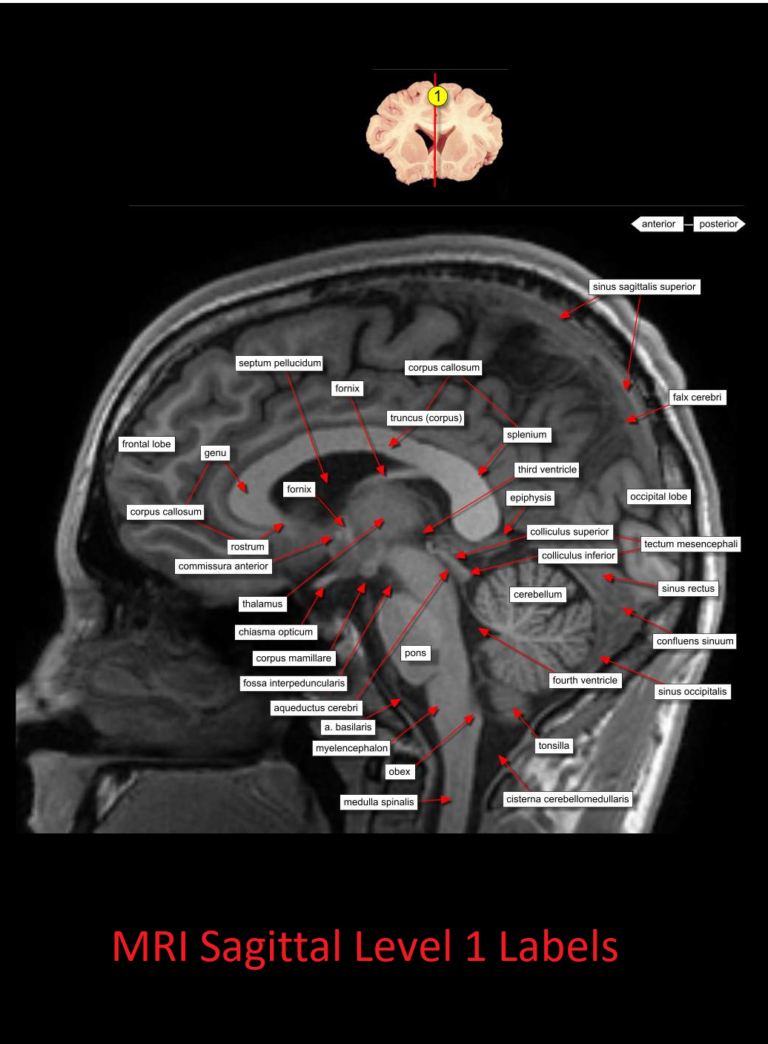

MRI Sagittal Anatomy of Brain Level 1 NCLEX Quiz Labelled Sagittal Mri Brain the labeled structures are (excluding the correct side): Look at midline image, from bottom to top: the mri is a particularly powerful exam for studying structures such as diencephalon, mesencephalon (mid brain), pons, myelencephalon. However, it takes longer to be produced than ct for example, which is why. sagittal mri brain, t1, with blank labels. this. Labelled Sagittal Mri Brain.

Labelled Sagittal Mri Brain . this article lists a series of labeled imaging anatomy cases by body region and modality. Use the mouse scroll wheel to move the. the biggest advantage of mri is that it uses no radiation. Look at midline image, from bottom to top: the labeled structures are (excluding the correct side): sagittal mri brain, t1, with blank labels. the mri is a particularly powerful exam for studying structures such as diencephalon, mesencephalon (mid brain), pons, myelencephalon. Temporal horn of lateral ventricle. However, it takes longer to be produced than ct for example, which is why. yuanhu yao et al., precision radiation oncology, 2023.